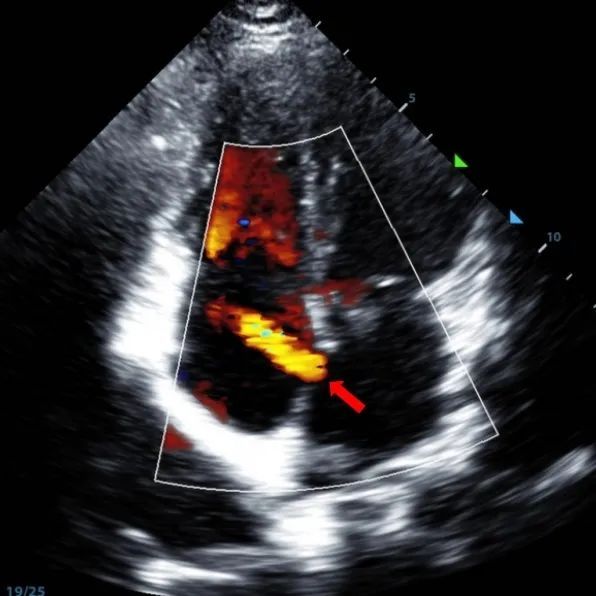

Secundum ASD (7.5〜7.9mm) の9歳の男性は、MemoSorb BDASD-I 12 mmオクルーダーおよび12Fデリバリーシステムを使用して治療されました。 手順前に合併症や併存症は見られませんでした。

Serial echocardiographic follow-ups showed stable device position and favorable cardiac remodeling. Gradual degradation confirmed the occluder's long-term safety and efficacy.